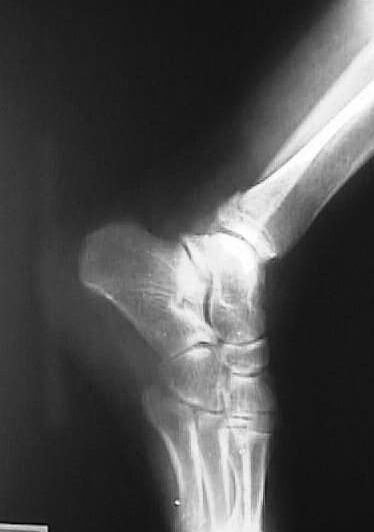

第7診 3月18日 (14日目)

X線撮影依頼(図7、8)。体重の付加を禁止したまま2週間経過。全身症状は良好。X線写真を見て骨折部位の整復・固定状況が不十分と判断、可能な限り正常な位置への復元が出来ないかを検討する。患部を触診し骨癒合が完全に行われていないと判断し、再度徒手整復を行う。中枢骨片がやや前下方に位置すると判断し、仰臥位にて末梢骨片を左手第2指で固定したまま、中枢骨片に左右の母指で前方より後方への圧迫を加え整復する。持続性を保つために生ゴムを用い、母指圧と同様の力が持続するようにテープを用いて固定した後、前日までと同様の固定を行う。

図7

図8